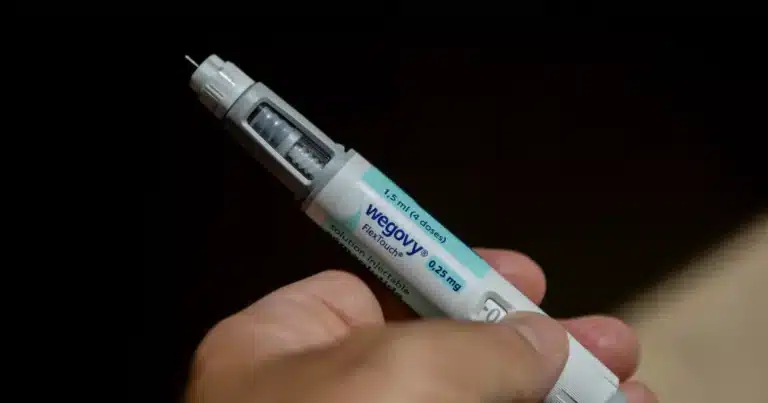

By – Rihem AkkoucheMillions of Medicare Enrollees Set for…

Millions of Medicare enrollees struggling with obesity are about to…